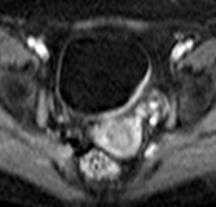

Инвазивная уротелиальная карцинома.

а)Т2-tra б) Т1-sag в)Т2-диффузия (DW)

Мужчина, 72 года. В заднее-левых отделах мочевого пузыря визуализирвется объемное образование (уротелиальная карцинома), стадия 3b.

(а) Аксиальное T2-взвешенное изображение показывает больших размеров опухоль с инвазией мышечной стенки и развитием гидроуретера (стрелка). Видна инвазия мышечного слоя, но достовено судисть о паравезикальном распространении невозможно.

(б) Динамическое контрастирование на скане, проходящем перпендикулярно к основанию опухоли выявляет тотальное поражение стенки пузыря, нечеткость заднего контура опухоли.

(в) Поперечное диффузионно-взвешенное изображение демонстрирует большую опухоль с признаками трансмурального роста и инвазии в паравезикальную клетчатку (стрелка).